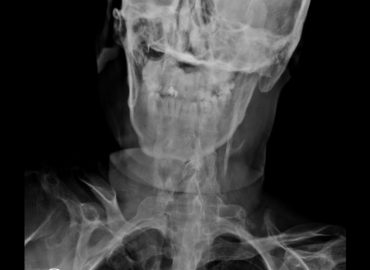

Paciente masculino de 36 años de edad. Motivo de consulta: odinofagia y rigidez mandibular.